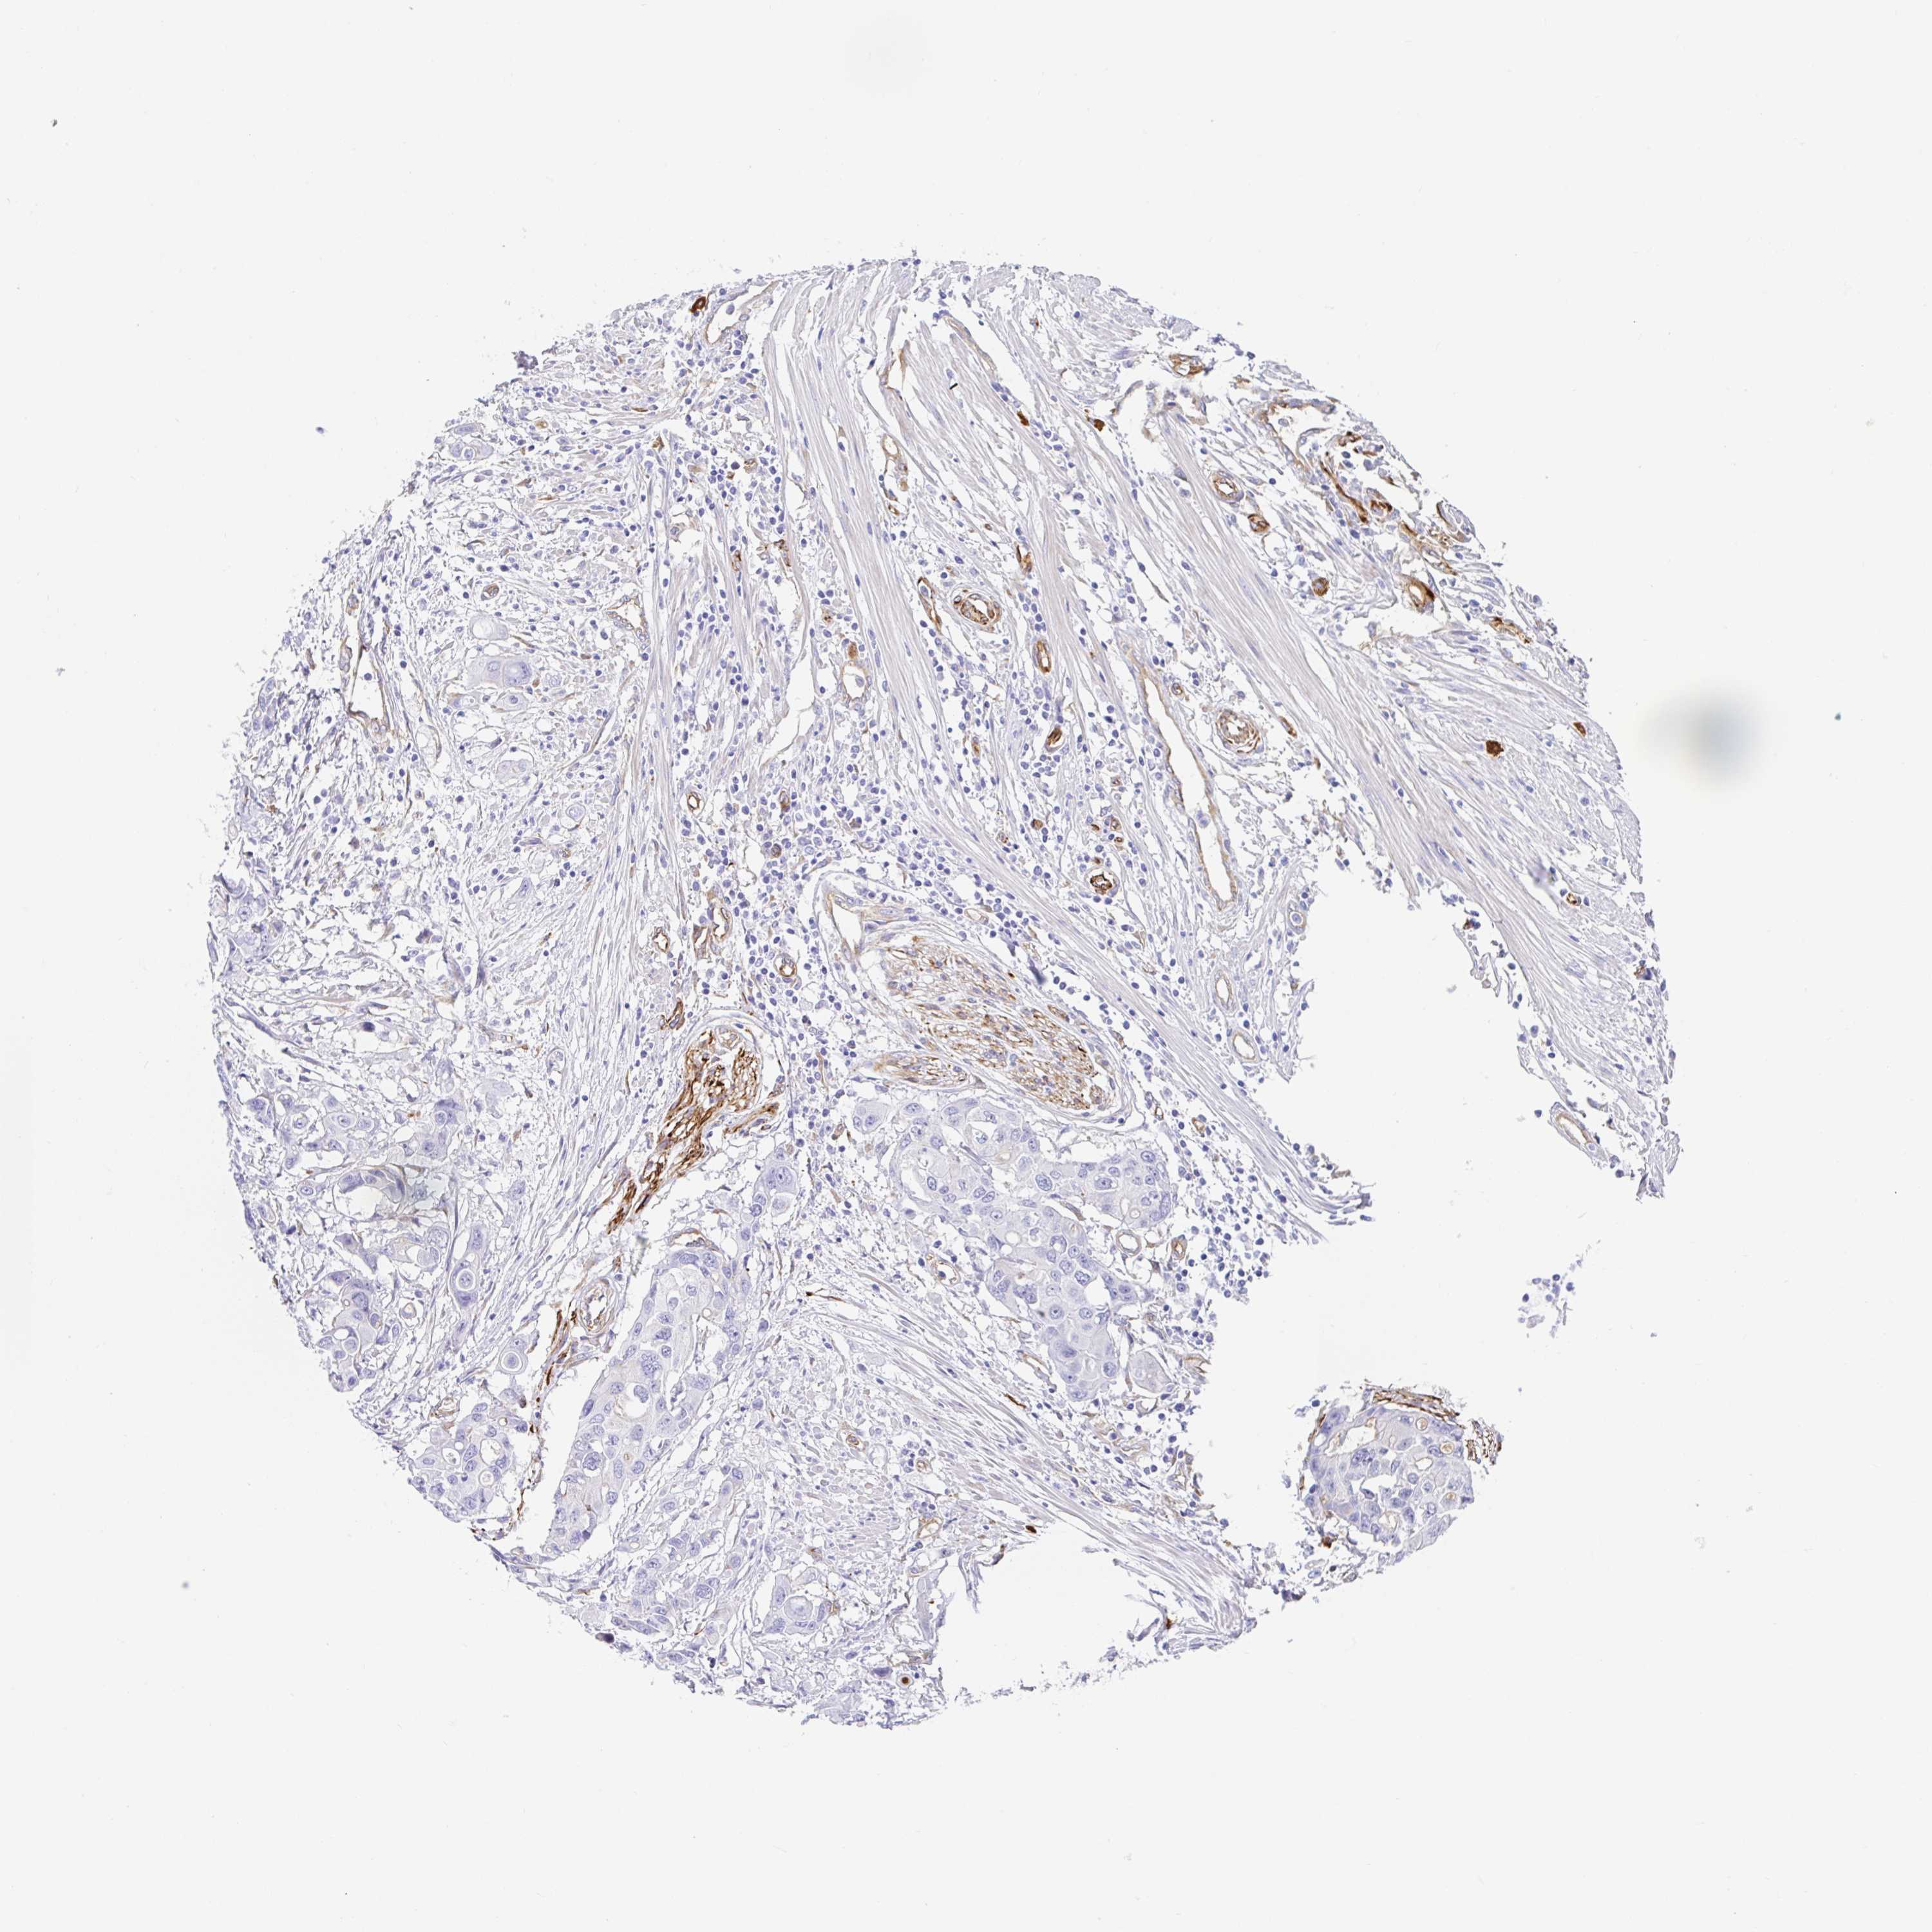

CANCER COLORECTAL CANCER Show tissue menu

Colorectal cancer

Human cancer

Colon adenocarcinoma